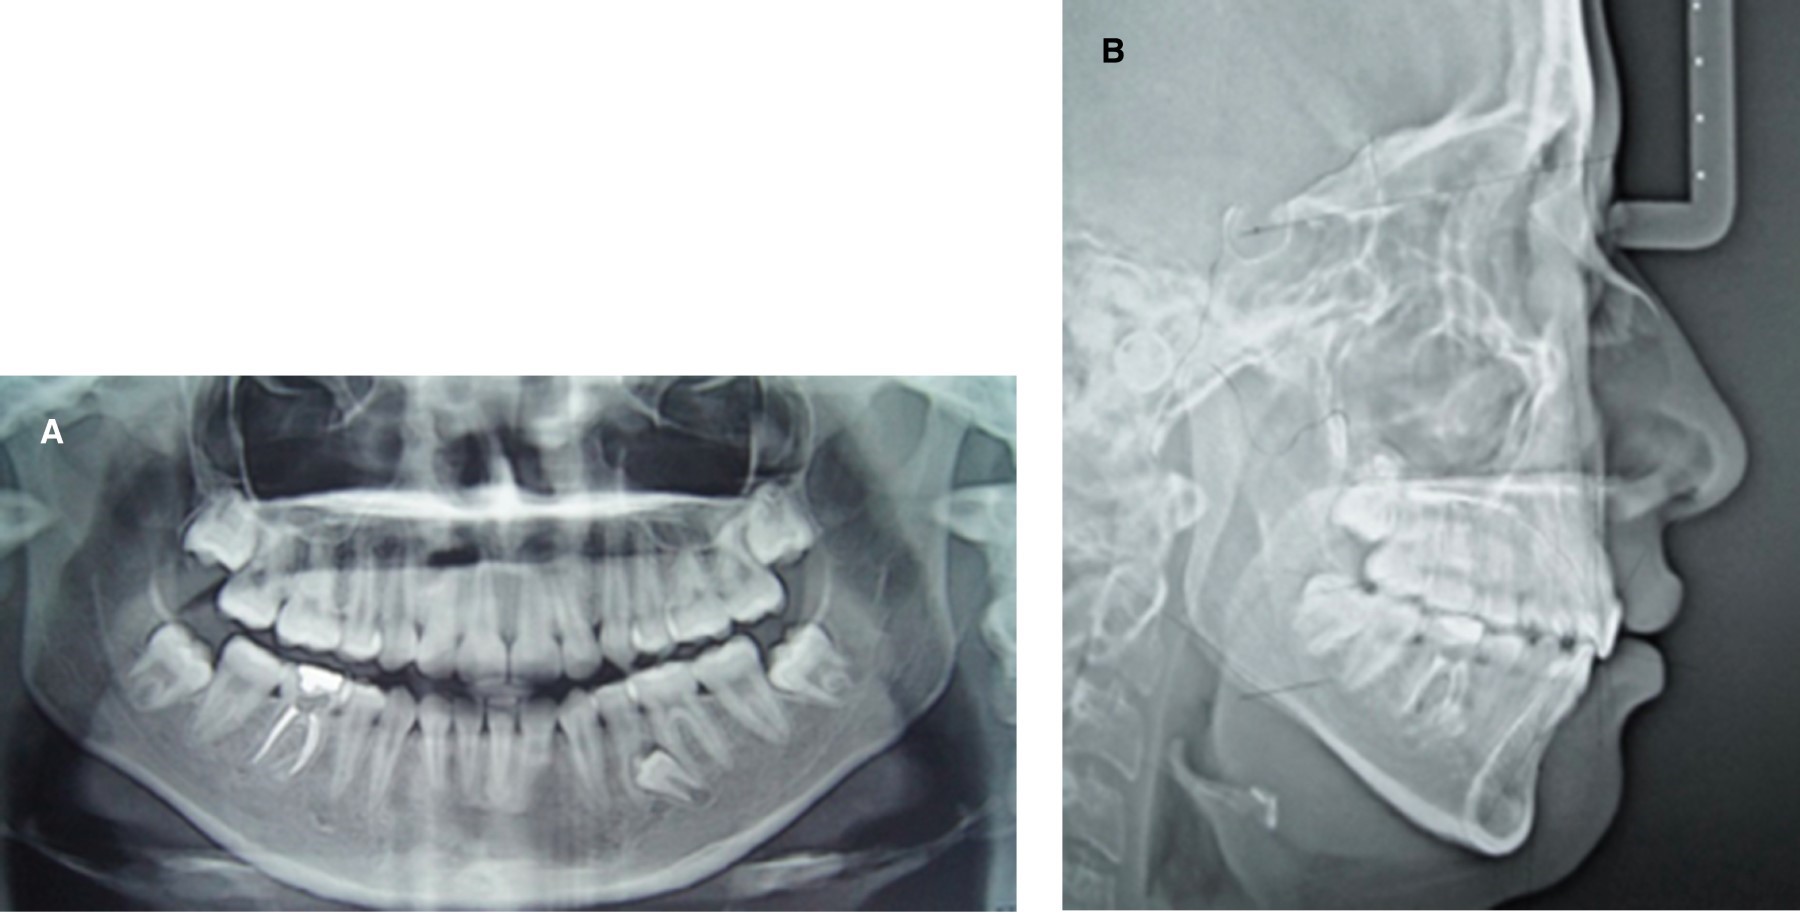

Extraoralmente hubo una disminución en la proyección del labio superior, lo que ayudó a mejorar el perfil facial y los cambios más significativos fueron intraorales. Se logró cerrar la mordida abierta con excelentes resultados estéticos, se mantuvo la relación clase I molar, se consiguió la relación canina de clase I con su respectiva guía canina y un overjet y overbite de 2 mm (Figura 6). El tiempo total de tratamiento fue de un año y 10 meses ininterrumpidos, terminando el caso con la mordida abierta corregida, con una relación clase I molar y canina, y una guía canina establecida (Figura 7A). Cefalométricamente los cambios más significativos fueron en los incisivos superiores que se retroinclinaron 8 mm, mientras que el IMPA quedó en 88o y el Wits en -1 mm (Tabla 1), en la Figura 7B y la superposición en la Figura 8 se observan los cambios dentales y esqueletales del paciente. Cabe señalar que la paciente presentó una mejora en su autoestima; en un principio se mostraba seria y al ver cómo su aspecto iba mejorando, mostró una actitud más positiva y llegaba con un entusiasmo muy notorio a sus citas de control. Al término del tratamiento, se remitió al Servicio de Cirugía Maxilofacial para extracción del diente supernumerario y terceros molares.

Figura 7